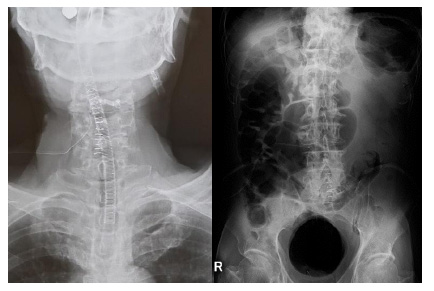

Magnetic resonance imaging (MRI) revealed spinal stenosis at C3/4, L4/5, and L5/S1 (Figs. 1 and 2). The right lesion at the level of L5/S1 appeared as a hyperintense area on both T1- and T2-weighted imaging in the thickened ligament flava. Computed tomography (CT) showed a high-density solitary lesion at this site, and we suspected an osseous tumorous lesion (Fig. 2).

Fig. (1). Magnetic resonance imaging of the cervical spine (sagittal and axial views). T2-weighted imaging shows severe stenosis of C3/4.